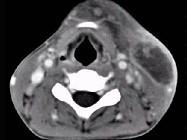

男性,67岁,颈部出现疼痛性肿块半年余,CT扫描如图所示,最可能的诊断是()A.神经鞘瘤B.囊肿C.淋巴结核D.淋巴瘤E.血管瘤

问题 男性,67岁,颈部出现疼痛性肿块半年余,CT扫描如图所示,最可能的诊断是()

选项 A.神经鞘瘤 B.囊肿 C.淋巴结核 D.淋巴瘤 E.血管瘤

答案 D